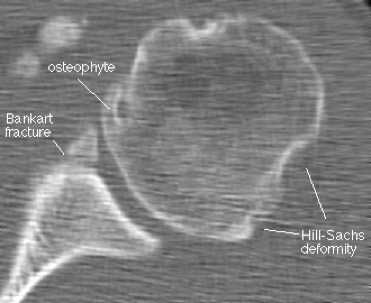

КТ при нестабильности плеча

А - дисплазия гленоида;

В - повреждение Хилл-Сакса (субхондральный перелом), дефект головки плечевой кости после вывиха плеча;

С - повреждение Банкарта (отрыв ободка от костной впадины с вывихом плеча вперед, разрушение краев лопаточной впадины - места прикрепления хряща);

D - повреждение Хилл - Сакса в переднем отделе суставной губы;

Е - 3D-реконструкция переднего вывиха плеча;

F- задний перелом с вывихом плеча.

Наиболее типичным (около 85% передних смещений травматической этиологии) является повреждение Банкарта - отрыв фиброзного или фибрознохрящевого фрагмента от края суставной впадины в месте прикрепления связки к суставной впадине с повреждением суставной губы. Кроме того, травма может приводить и к костным повреждениям - перелому гленоидного кольца спереди, костному повреждению Банкарта (то есть повреждению Банкарта в сочетании с переломом) и перелому большой бугристости.

МРТ плечевого сустава. Корональные Т1-взвешенные МРТ. Переломы Хилла-Сакса и Банкарта.

На КТ хорошо видны костные дефекты и дефекты гиалинового хряща суставной впадины. Гиалиновый хрящ, покрывающий головку плечевой кости виден гораздо хуже.

КТ плечевого сустава, Переломы Банкарта и Хилла-Сакса.